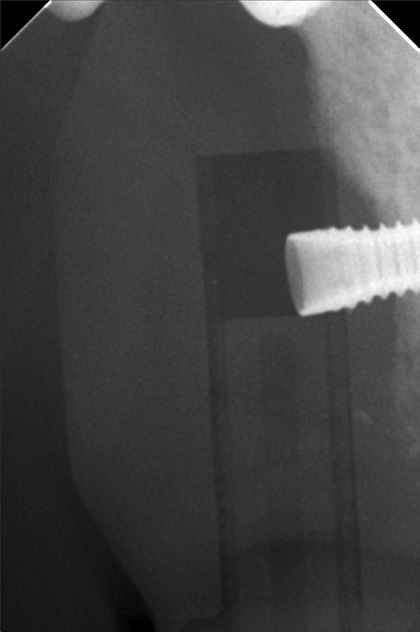

- Procedure